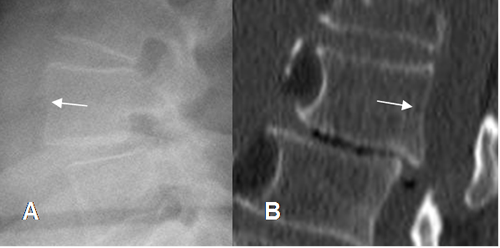

La listesis se nombra de acuerdo a la dirección del desplazamiento de la vértebra superior. (6). (Fig 71).

Se aprecia como imagen radiolúcida en la pars interarticular, con esclerosis de los fragmentos, mejor visto en una Rx oblicua. Puede ser uni o bilateral. En la TAC se encuentran los mismos hallazgos, en cortes por encima del nivel del disco. (1). (Fig 72 a 74).

Fig 71. Denominación de listesis.

A: Rx lateral. Anterolistesis con desplazamiento anterior del cuerpo superior.

B: TAC reconstrucción sagital. Retrolistesis con desplazamiento posterior del cuerpo superior.